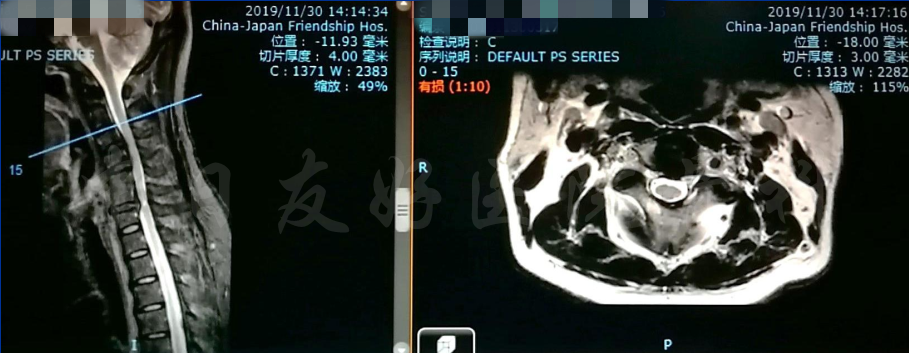

MRI

MRI颈4-5(左)、颈5-6(中)颈6-7(右)

矢状位MRI

轴位MRI:腰3-4(左)、腰4-5(中)、腰5骶1(右)

颈椎MRI

颈椎MRI

颈椎各节段MRI(上下滑动)

腰椎MRI